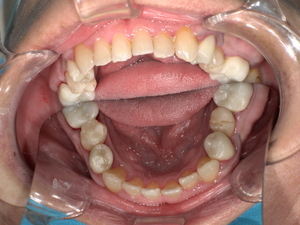

Before:白い詰め物がとれて、見た目も清潔感に欠ける状態。

After: セラミックで修復され、天然歯のように自然な白さと透明感がある美しい歯の状態。どこが治療箇所か分からないほど自然な白さへ。